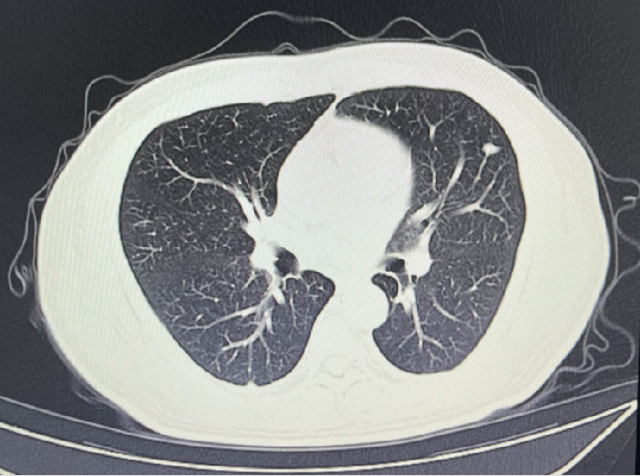

影像学检查

2024-02-28: